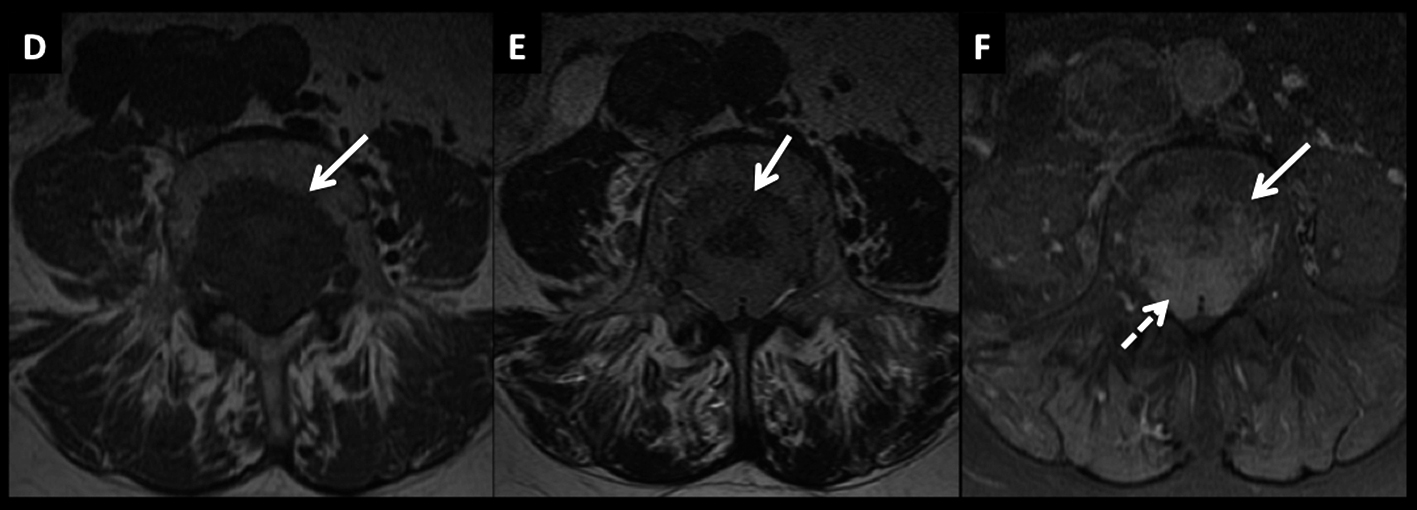

LNH, lesiones óseas y masa extradural, compromiso secundario.

Paciente con LNH sistémico, que presenta dolores óseos progresivos y un síndrome de medular asociado.

En RM, secuencia T2 sagital (A) se observan múltiples pequeñas lesiones óseas (*) heterogéneas, y una masa de partes blandas a nivel dorsal bajo, intra-raquídea, extradural, de baja señal en T2 con desplazamiento y compresión del cordón medular (flecha discontínua).

En secuencia T1 (B) es de baja señal y luego de administrar contraste presenta intenso realce, homogéneo (C).

Figura 4

LNH, lesiones óseas y masa extradural, compromiso secundario. (cont)

En el plano axial (D secuencia T2, E secuencia T1 y F secuencia T1 con contraste) se observa la masa descrita con un patrón de crecimiento que lo “amolda” al canal y se extiende a los espacios vecinos a través de los neuro-forámenes del nivel seleccionado.